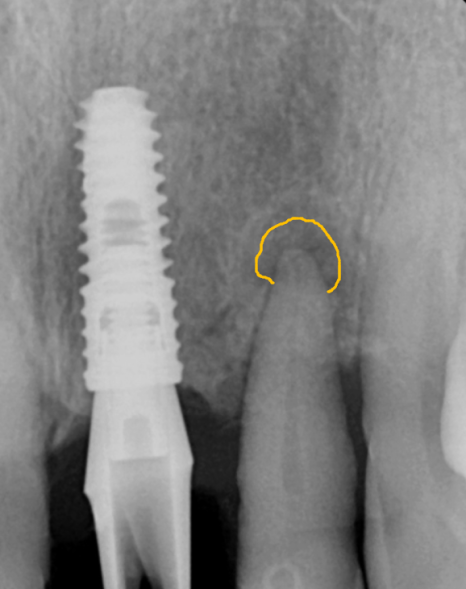

방사선 사진상, 뿌리끝 염증으로

뼈가 녹은 부위가 있었고,

뼈 폭도 얇아 임플란트만 식립하기엔

무리가 있어 보였습니다.

231107

그래서 뼈이식과 함께

임플란트 수술을 진행하는 것으로

계획을 세웠습니다.

뿌리끝 염증이 있던 케이스는

염증 조직(육아조직)을

남기지 않는 게 정말 중요합니다.

이 염증조직들을

제대로 제거하지 않으면

애써 심어 놓은 임플란트도

이 녀석들 때문에

뼈가 녹아 문제가 생기거든요.

그래서 잇몸을 절개한 뒤

염증 조직을 직접 눈으로

확인하며 깔끔하게 제거했고,

깨끗해진 뼈에

뼈이식을 충분히 시행했습니다.